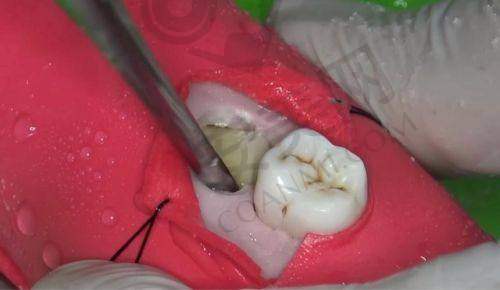

为了提高智齿拔除的正确性和安心性,玉溪舒尔口腔医院引进了一系列精良的设备。其中,口腔CT设备能够清晰地显示智齿的位置、形态以及与周围组织的关系,帮助医生制定更精细的手术方案。在拔除智齿时,使用的超声骨刀可以严谨地切割牙槽骨,减少对周围组织的损伤,降低患者的疼痛感和术后并发症的发生几率。此外,医院的消毒设备也非常精良,能够确保手术器械的严格消毒,避免交叉感染,为患者提供一个安心、卫生的治疗环境。